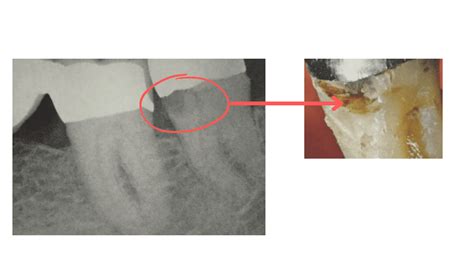

When looking at your own X-rays on a monitor, you might find them confusing. Dentists are trained to identify specific visual cues. In a tooth decay X-ray, enamel—the hardest substance in your body—appears as a bright white or light gray area. Healthy bone also shows up in varying shades of white. When tooth decay is present, it appears as a darker, shadowy spot on the image.

This happens because the demineralization caused by bacteria makes the tooth structure less dense, allowing more X-ray radiation to pass through the area. The less dense the tissue, the darker it appears on the radiograph. If your dentist points out a dark spot on your X-ray, they are identifying an area where the mineral content of your tooth has been compromised by acid-producing bacteria.